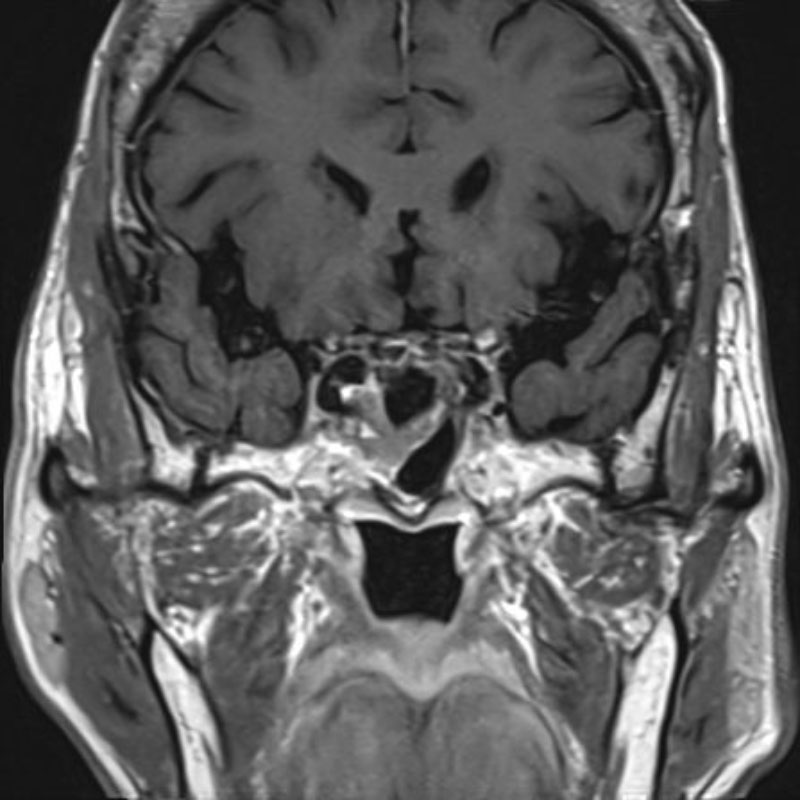

No.’25_74 手術前1

No.’25_74 手術前2